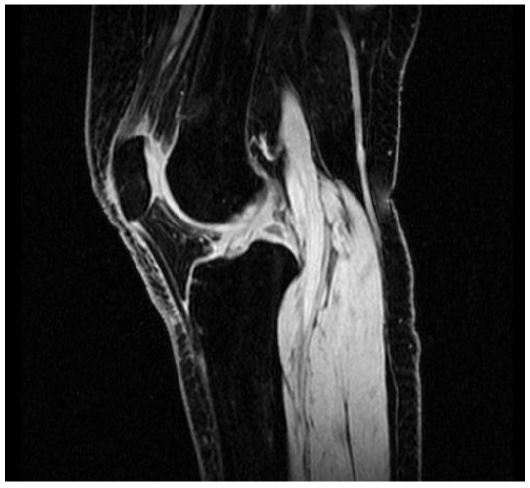

HIGH-RES SAGITTAL